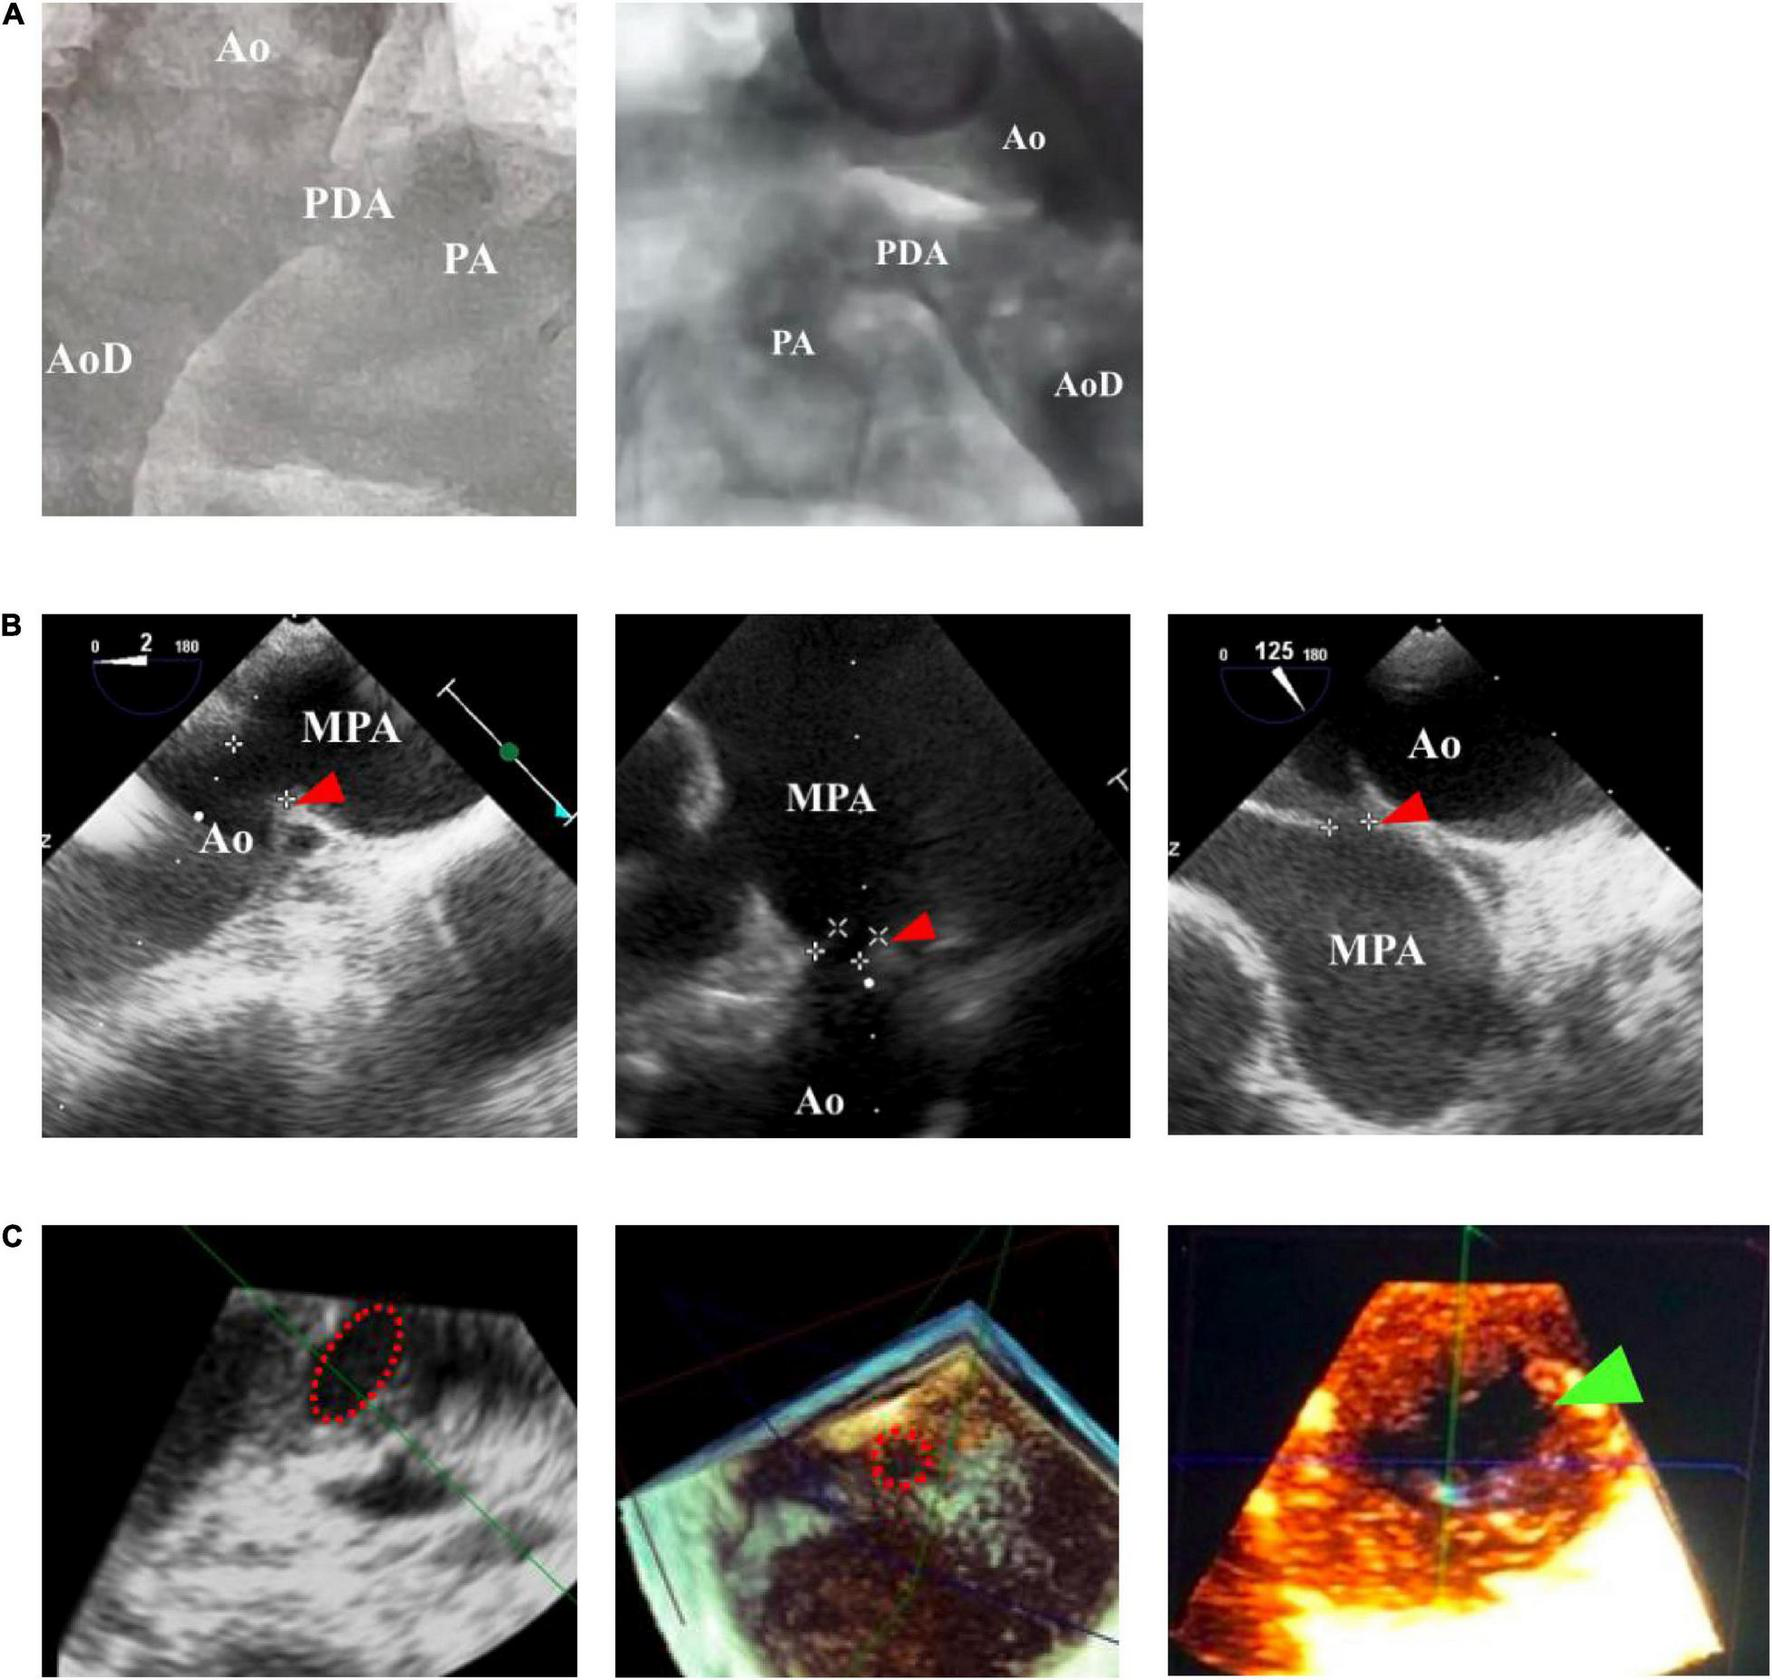

FIGURE 1

Comparison of patent ductus arteriosus (PDA) size and morphology measurements using fluoroscopy and echocardiography guidance. (A) Fluoroscopy can only provide a 2-dimensional image, whereas (B) transthoracic echocardiography (TTE) and transesophageal echocardiography (TEE) can provide a 3-dimensional structure as shown by the red arrowhead. (C) Cross-sectional PDA morphology measured by using transesophageal echocardiography (TEE), indicated by the dotted red circle. Green arrowhead showed oval-shaped PDA. Ao, aorta; AoD, descending aorta; MPA, main pulmonary artery; PA, pulmonary artery.